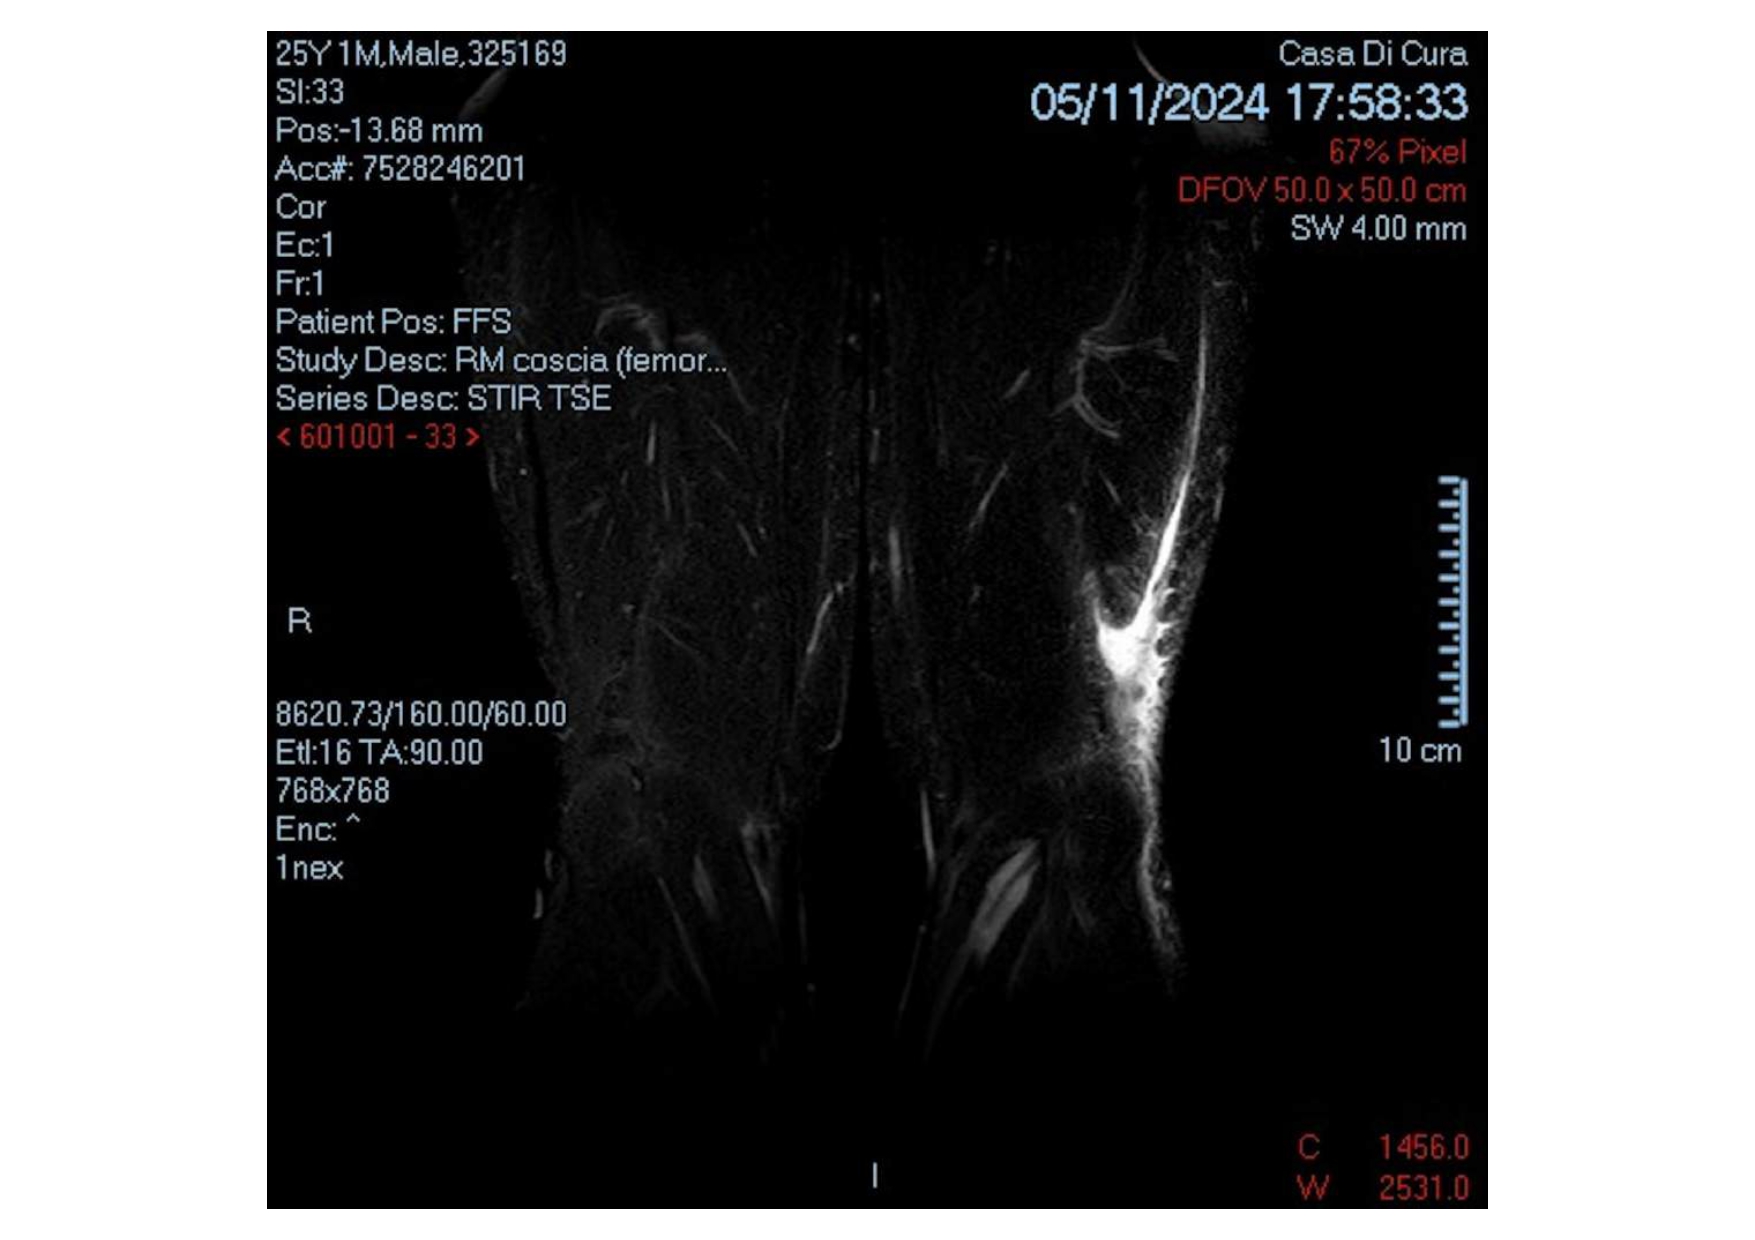

Currently, there is no established consensus or guideline on the most appropriate rehabilitation program following surgical reconstruction of the biceps femoris tendon in professional athletes. Consequently, rehabilitation interventions, outcome measures, and timelines remain unclear, therefore, the aim of this case report is to provide an accurate description of the programme and timeline about rehabilitation in a 25 year old elite rugby player who underwent surgery following distal lesion of biceps femoris tendon.